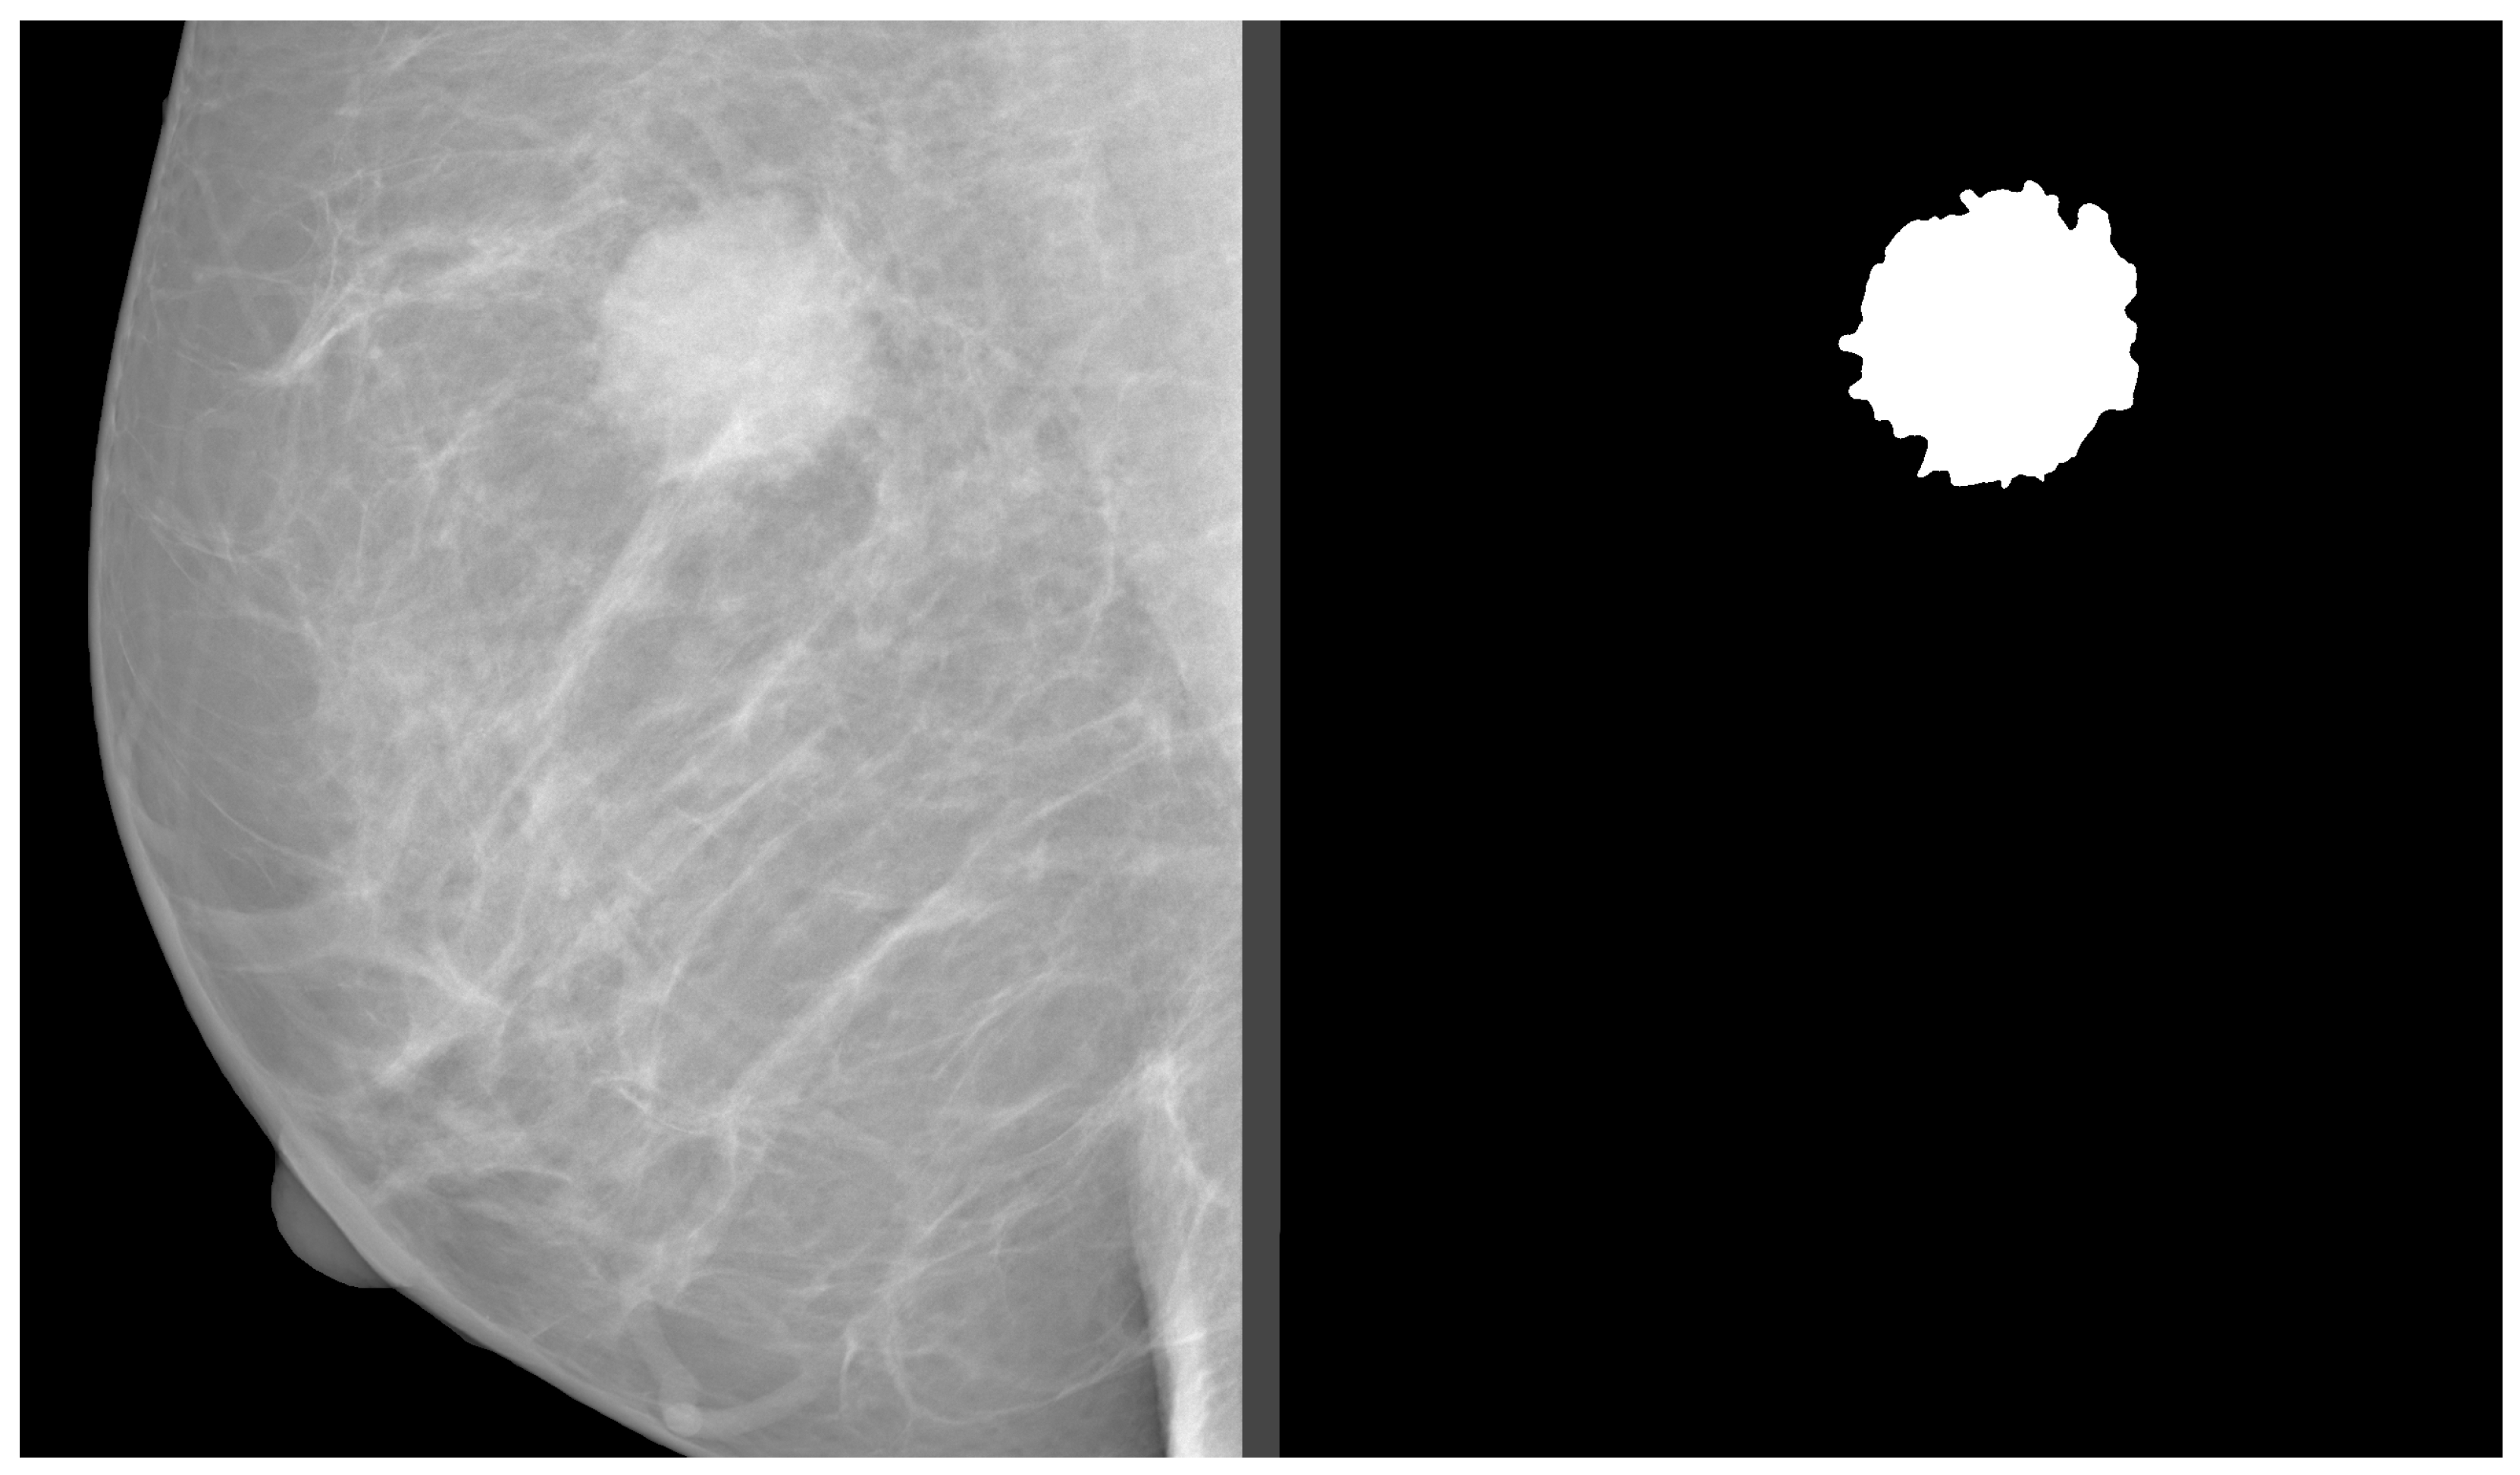

3. Open-Access Databases

In our study, we analyzed mammography databases that contained information about the boundaries and malignancy of findings. The region of interest (ROI) can be defined in several ways, with the most common method being a binary mask (as shown in Figure 9). The mask is an image with the same resolution as the observed image, where pixels have only two values. The first value (usually 0) represents the background, while the second value (usually 1 or 255) represents the ROI. Alternatively, the ROI can be defined by the coordinates of the center with the radius of a circle around the ROI, or by contours around the ROI. These databases are of significant value for neural network models, as training with whole images would be more complex and time-consuming. Even databases with only image-level labels have value in deep learning, for example, they can be used for fine-tuning a model. A summarized overview of the analyzed datasets (excluding the OMI-DB, as the amount of data may vary) is shown in Figure 10 and Table 4, while more detailed statistics of the individual datasets are provided in Figure 11, Figure 12 and Figure 13.

Figure 9. Binary mask of mass finding. Source: [11].